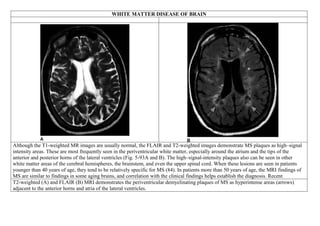

WHITE MATTER DISEASE OF BRAIN

Although the T1-weighted MR images are usually normal, the FLAIR and T2-weighted images demonstrate MS plaques as high–signal

intensity areas. These are most frequently seen in the periventricular white matter, especially around the atrium and the tips of the

anterior and posterior horns of the lateral ventricles (Fig. 5-93A and B). The high–signal-intensity plaques also can be seen in other

white matter areas of the cerebral hemispheres, the brainstem, and even the upper spinal cord. When these lesions are seen in patients

younger than 40 years of age, they tend to be relatively specific for MS (84). In patients more than 50 years of age, the MRI findings of

MS are similar to findings in some aging brains, and correlation with the clinical findings helps establish the diagnosis. Recent

T2-weighted (A) and FLAIR (B) MRI demonstrates the periventricular demyelinating plaques of MS as hyperintense areas (arrows)

adjacent to the anterior horns and atria of the lateral ventricles.